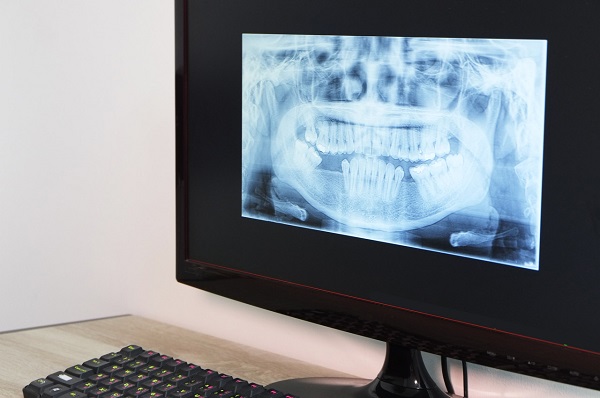

在口腔醫學領域,種植牙是一項神奇而又重要的技術,為許多失去牙齒的人帶來了新的希望。當患者決定進行種植牙手術時,首先會進行詳細的口腔檢查和評估。醫生會通過 X 光、口腔掃描等手段,了解患者口腔的整體狀況,包括牙槽骨的密度、高度以及寬度等情況,以判斷患者是否符合植牙手術條件。